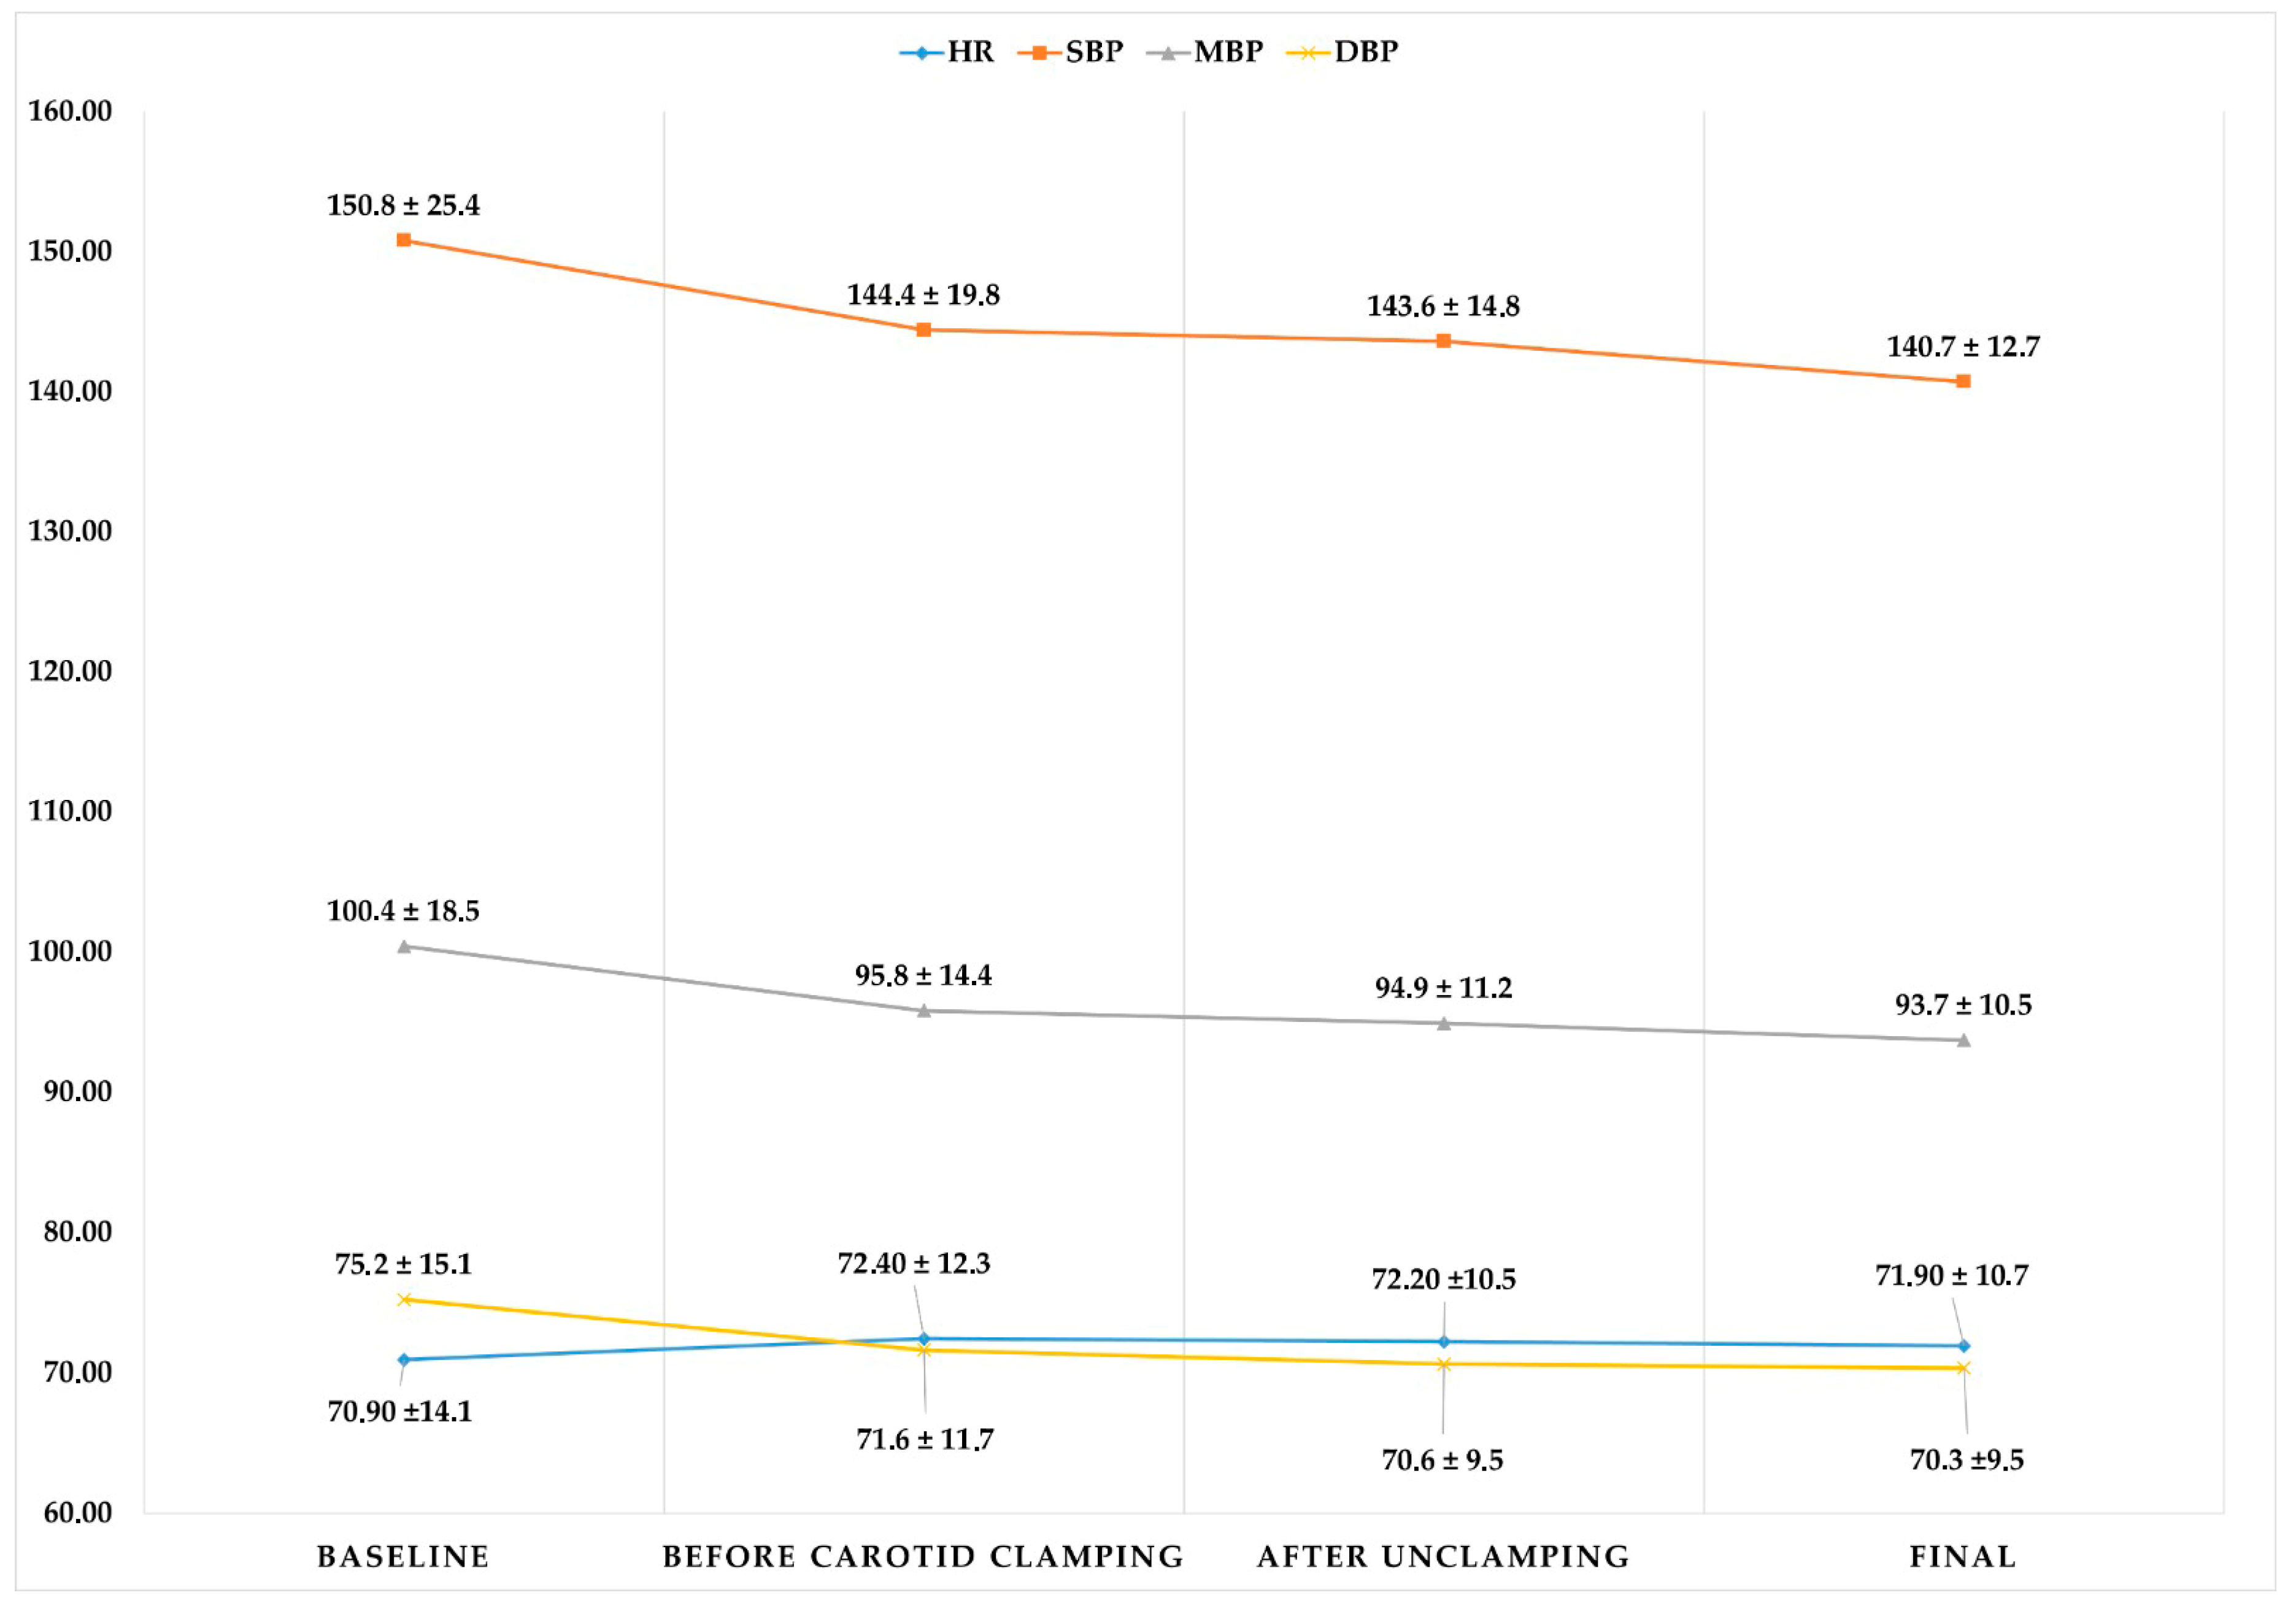

3. Results